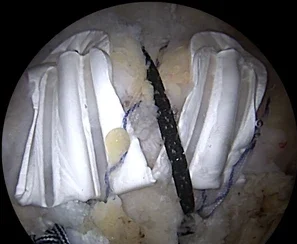

Rotator cuff repair techniques have advanced significantly, yet healing failure after surgery remains a common challenge. Even with modern arthroscopic fixation and double-row constructs, healing ultimately depends on the biologic environment of the repaired tendon. For surgeons managing larger tears, compromised tissue quality, or revision repairs, augmentation strategies are becoming an increasingly important part of the treatment algorithm. Arthroscopic rotator cuff repair has become the standard of care for symptomatic full-thickness tears and cases that fail nonoperative treatment. However, despite advances in surgical techniques and fixation technology, retear rates can still range from roughly 20% to 90% depending on tear size and repair strategy. These persistent challenges have driven increasing interest in rotator cuff augmentation techniques, particularly the use of scaffold implants designed to reinforce the repair and support biologic healing. Why Rotator Cuff Repairs Sometimes Fail Traditional rotator cuff repairs primarily address the mechanical fixation of tendon to bone using sutures and anchors. While this provides strong initial stability, successful healing ultimately depends on the biologic response of the tendon. Several factors can compromise healing, including: One of the most common failure mechanisms occurs when sutures cut through weakened tendon tissue, leading to loss of fixation before the tendon has fully healed. Because of this, many surgeons are exploring augmentation strategies that reinforce the repair construct while supporting the biologic healing environment. How Biologic Scaffolds Support Rotator Cuff Healing Biologic scaffolds are designed to provide a temporary structural matrix that interacts with the body’s natural healing processes. Synthetic grafts used in rotator cuff augmentation have been shown to demonstrate biomechanical properties similar to native rotator cuff tendon, including comparable stiffness and maximal load to failure. When used during repair, scaffold implants may help: Surgeons interested in the underlying scaffold design principles can explore the science behind Atreon’s tendon healing technology. BioCharge® Autobiologic Matrix for Rotator Cuff Augmentation One augmentation option is BioCharge® Autobiologic Matrix, a bioresorbable synthetic scaffold engineered with PGA & PLCL that mimics the native ECM. Designed as a bioinductive scaffold that promotes cellular activity and collagen remodeling by wicking the patient’s own biologic factors to the repair site, the scaffold supports the native healing process of the tendon. The implant is positioned on the bursal side of the tendon, where it reinforces the surface of the repaired cuff and supports healing at the tendon–suture interface. BioCharge is designed to: Learn more about the implant and surgical workflow on the BioCharge Autobiologic Matrix product page. Visualizing the BioCharge Technique To help surgeons visualize the procedure, Atreon Orthopedics has developed a surgical animation demonstrating BioCharge augmentation during rotator cuff repair. Surgical Technique: Augmented Double-Row Rotator Cuff Repair A recently published surgical technique describes how BioCharge can be incorporated into a double-row arthroscopic rotator cuff repair. The procedure begins with standard arthroscopic evaluation of the shoulder joint followed by entry into the subacromial space. After bursectomy and visualization of the tear, the rotator cuff footprint is prepared until adequate bone bleeding is achieved to promote healing. Once the medial row anchors are placed and sutures are passed through the tendon: The final repair creates a double-row construct with BioCharge augmentation, increasing footprint compression while allowing the scaffold to wick local biologic factors into the repair environment. Improving Biologic and Mechanical Healing in Rotator Cuff Repair Rotator cuff surgery continues to evolve beyond mechanical fixation alone. Increasingly, surgeons are focusing on the biologic environment surrounding the repair, recognizing that tendon healing depends on both structural stability and cellular activity. Tools like the Rotator Cuff Healing Index (RoHI) help surgeons identify higher-risk cases where healing may be compromised. In these situations, augmentation technologies such as BioCharge Autobiologic Matrix may help reinforce the repair and support the biologic healing process. Atreon Orthopedics continues to develop technologies designed to improve tendon healing from multiple biological perspectives. In addition to BioCharge, the ROTIUM® Bioresorbable Wick supports healing at the tendon-bone interface during rotator cuff repair. References Disclaimer BioCharge® Autobiologic Matrix is intended for use as an adjunct to surgical rotator cuff repair. Surgeons should consult product labeling and instructions for use before implantation.